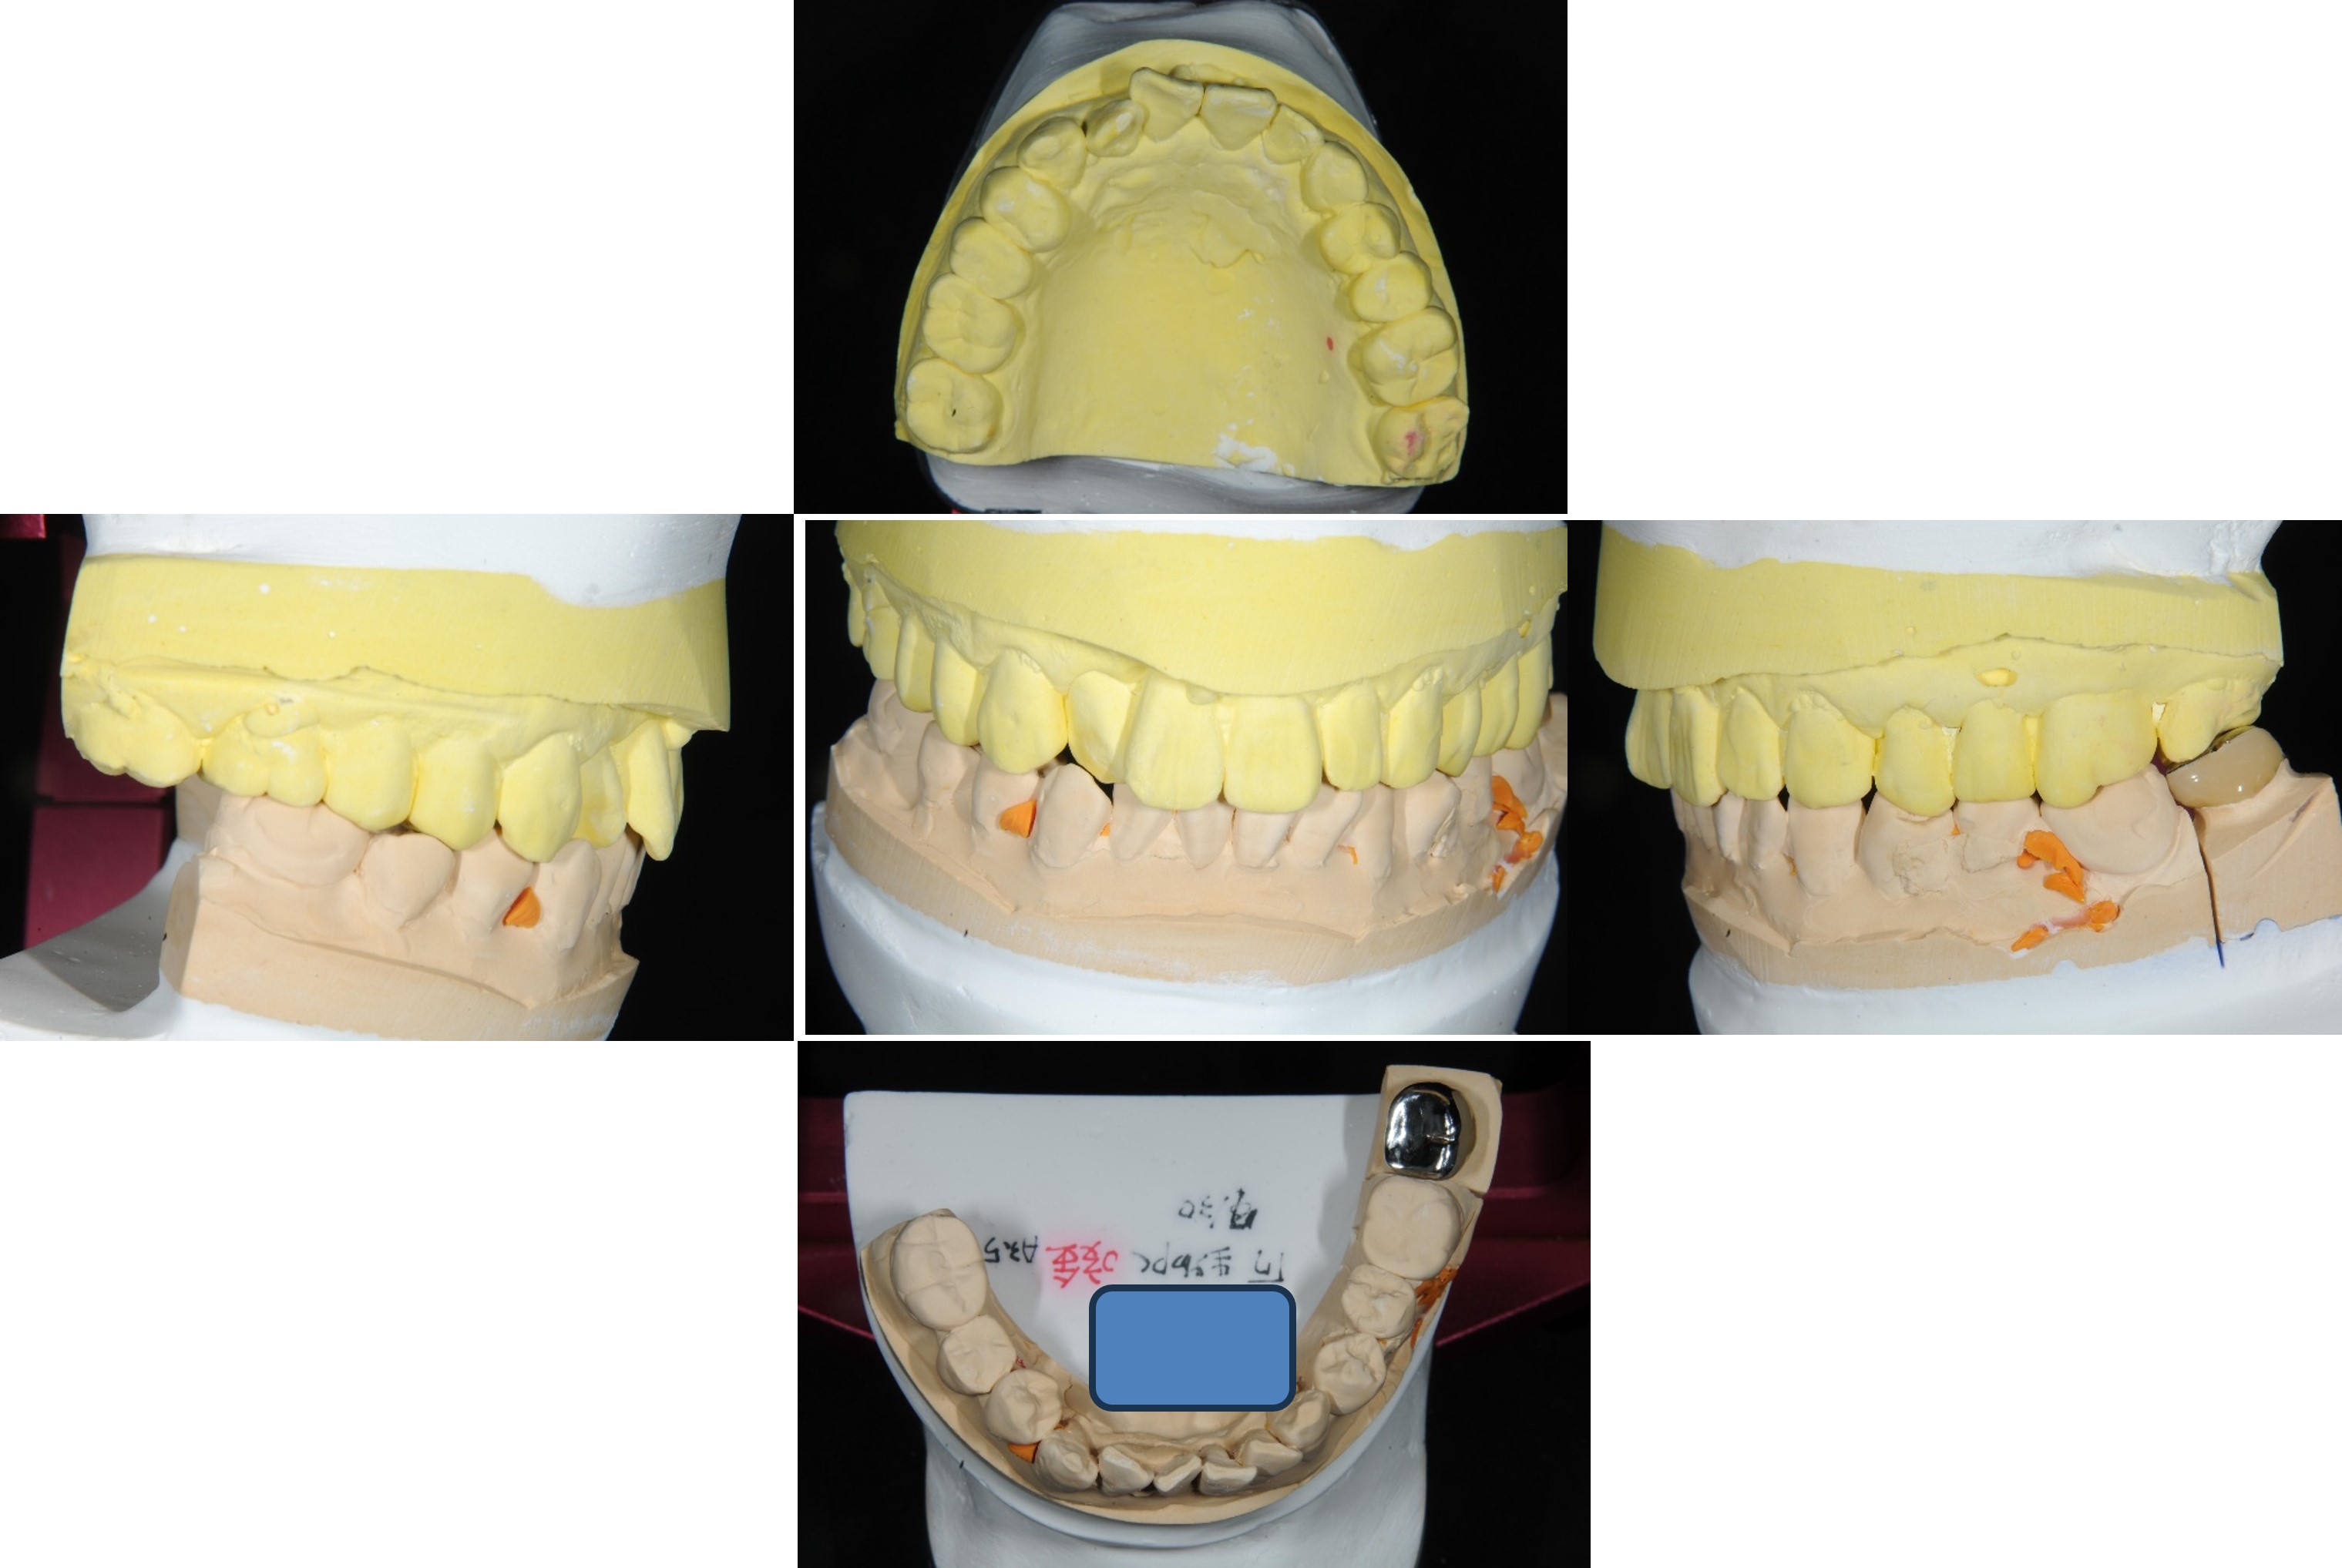

於半調節咬合器製作假牙

咬合器製作假牙

金屬燒付瓷牙